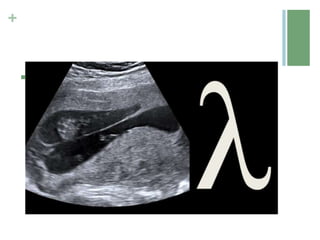

 In dichorionic twins there is a V shape extension of placental

tissue into the base of the intertwin membrane (Lambda or twin

peak sign).